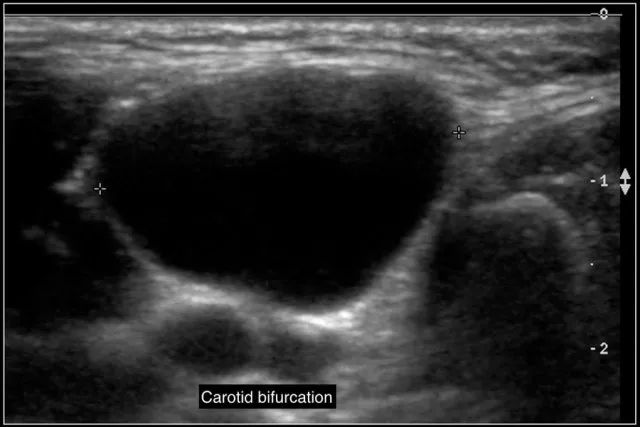

Carotid Body Tumor (Paraganglioma)

- Pulsatile mass at carotid bifurcation.

- Mobile side-to-side, not vertically (Fontaine's sign).

- "Lyre sign" on angiography.